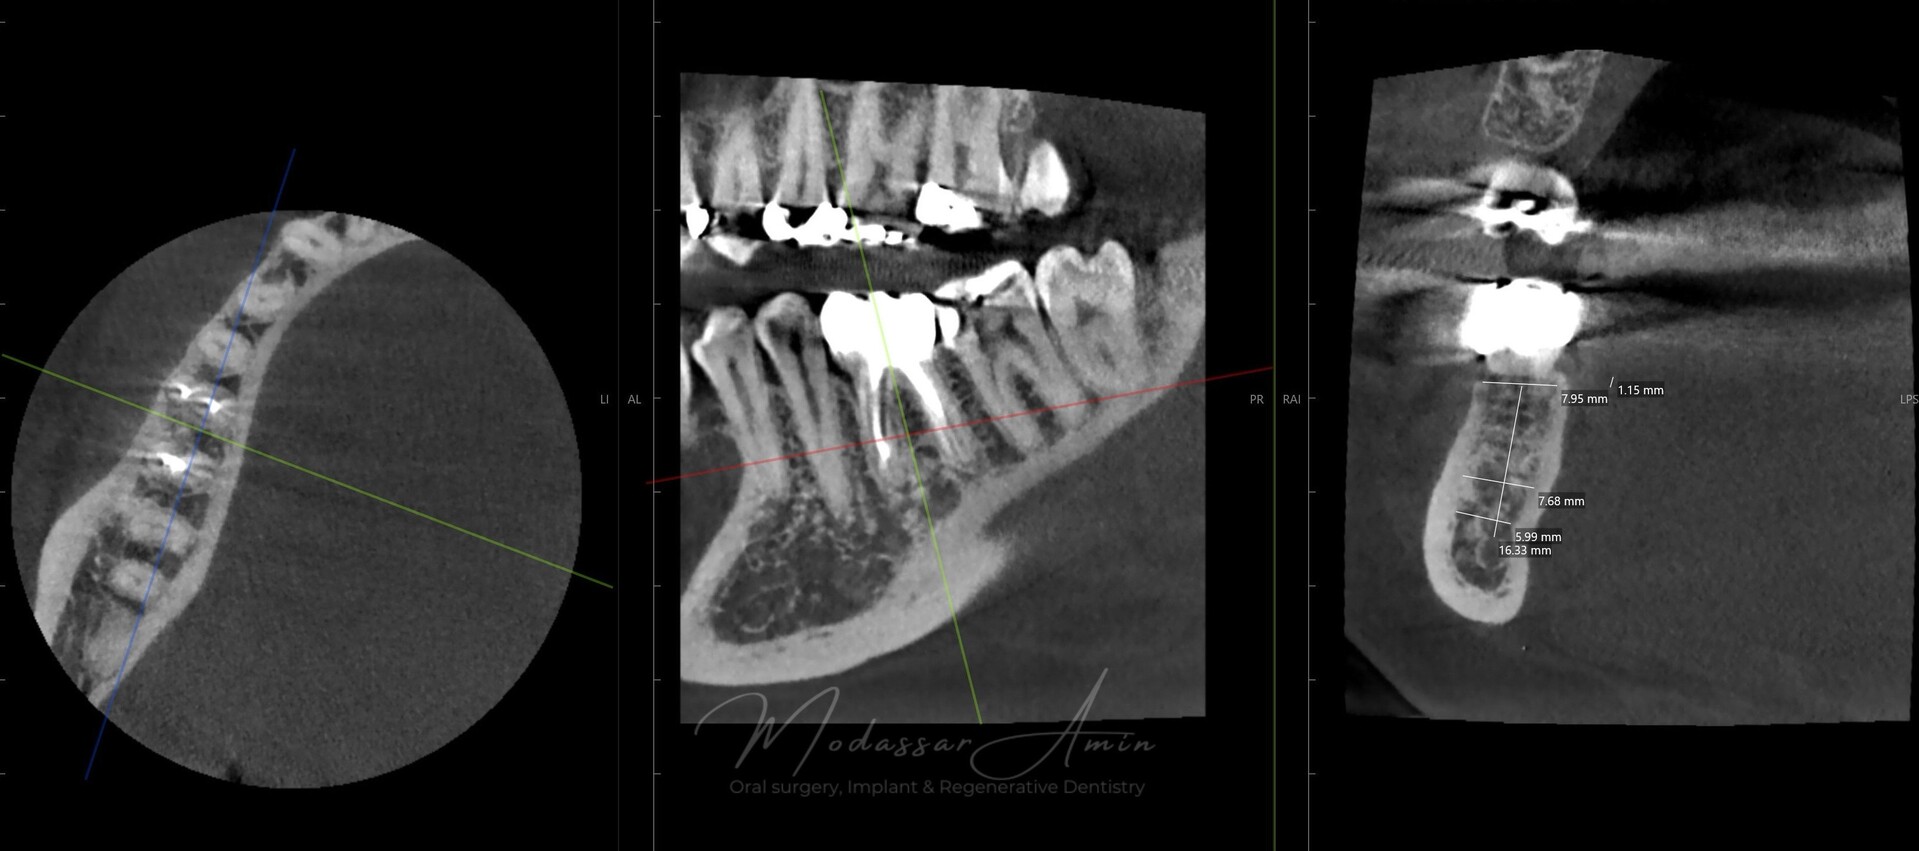

Pasienten presenterte med tann 46 som ikke kunne bevares grunnet en dyptgående infraksjon inn i furkasjonen. Forholdene lå til rette for en immediate implantatbehandling. Ved hjelp av Versah osseodensifikasjonsbor ble det interradikulære beinet ekspandert på en skånsom og forutsigbar måte, noe som ga høy primærstabilitet (>40 Ncm) til tross for en lokal bendefekt apikalt mesialt etter kronisk apikal periodontitt. Den gode stabiliteten muliggjorde bruk av SSA (Sealing Socket Abutment) for forsegling. På grunn av tynn bløtvevsfenotype bukkalt ble behandlingen supplert med bindevevstransplantat (CTG):

CBCT røntgen